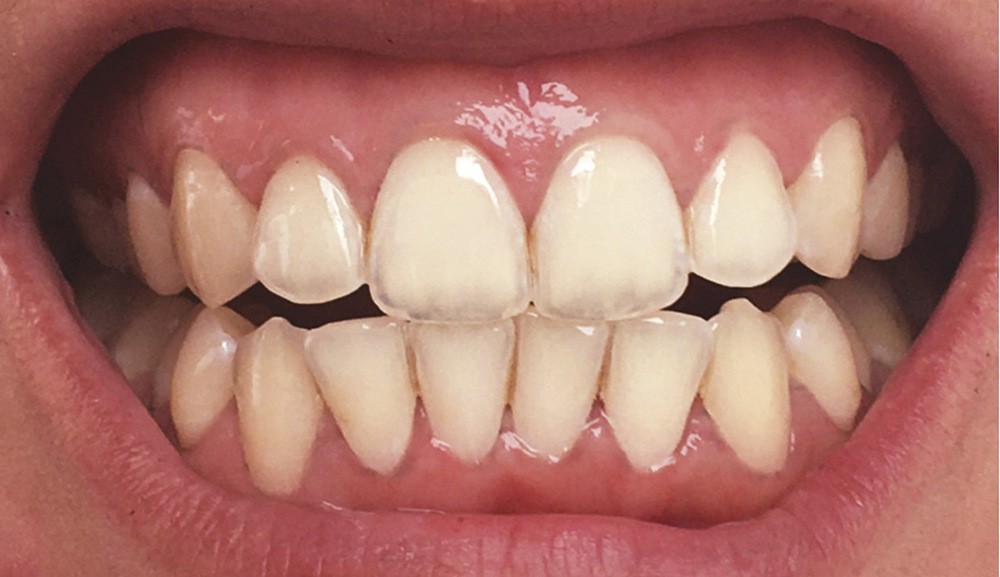

Les modifications hormonales à mettre en relation avec l’hygiène bucco-dentaire, les paramètres socio-économiques, l’âge précoce de la grossesse ainsi que l’augmentation du grignotage pourraient augmenter la prévalence des caries dentaires chez la femme enceinte. Ces patientes sont régulièrement sujettes à des envies multipliant le nombre de prises alimentaires souvent très riches en sucre. Ces apports sucrés, associés à la baisse du pH salivaire lors de la grossesse, entraînent un déséquilibre du cycle déminéralisation et de reminéralisation. Le risque carieux peut être augmenté, ainsi que la susceptibilité à l’érosion dentaire accrue par les vomissements et/ou les reflux gastro-œsophagiens [2]. L’action hormonale peut également avoir des répercussions sur les tissus parodontaux. La gingivite gravidique observée sur plus d’une femme enceinte sur deux, constitue une réponse inflammatoire de la gencive exacerbée par la présence de plaque bactérienne, et favorisée par l’augmentation des taux d’œstrogène et de progestérone [3] (fig. 1). 5 % des futures mères développeront un épulis, dont l’étiologie reste méconnue (fig. 2) [4].